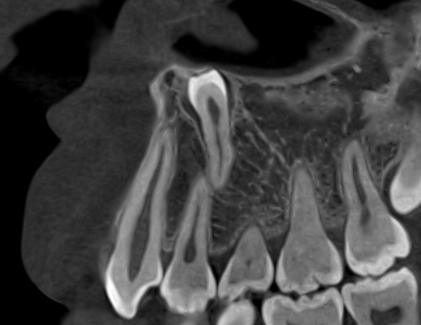

☆本院特別巨資增設 ”千萬級3D AI透視電腦斷層”,並配合“成骨膠原蛋白”施作 (上述兩項目前健保無給付),讓您遠離神經傷害、口鼻竇(炎)相通...等併發症,除健保之外,難免會有避免併發症風險的自費項目,網路上經常會有看到智齒拔完後唇麻、舌麻、口鼻竇相通等併發症,在本院嚴格自我要求下,此類併發症在本院幾乎趨近於零。

(兩條紅線中間黑色區域即為神經管)

外面拔完時常術後唇麻舌麻,本院發生趨近於零